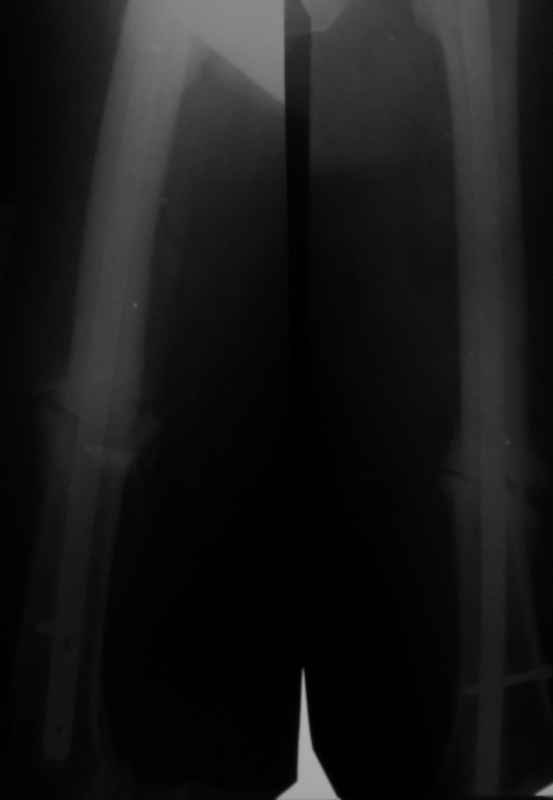

Больной 52л. с переломами обеих бедер 1 годичной давности. Лечился гвоздями Chm.

Справа перелом сросся, слева формируется псевдартроз,ротационная подвижность(после динамизации остался один винт в дистальном отверстии штифта). Активная тактика - удалить гвоздь, рассверлить канал, поставить более толстый. Есть ли ей альтернатива,но не менее эффективная?

У пациента Гипертрофический Ложный Сустав Бедра.